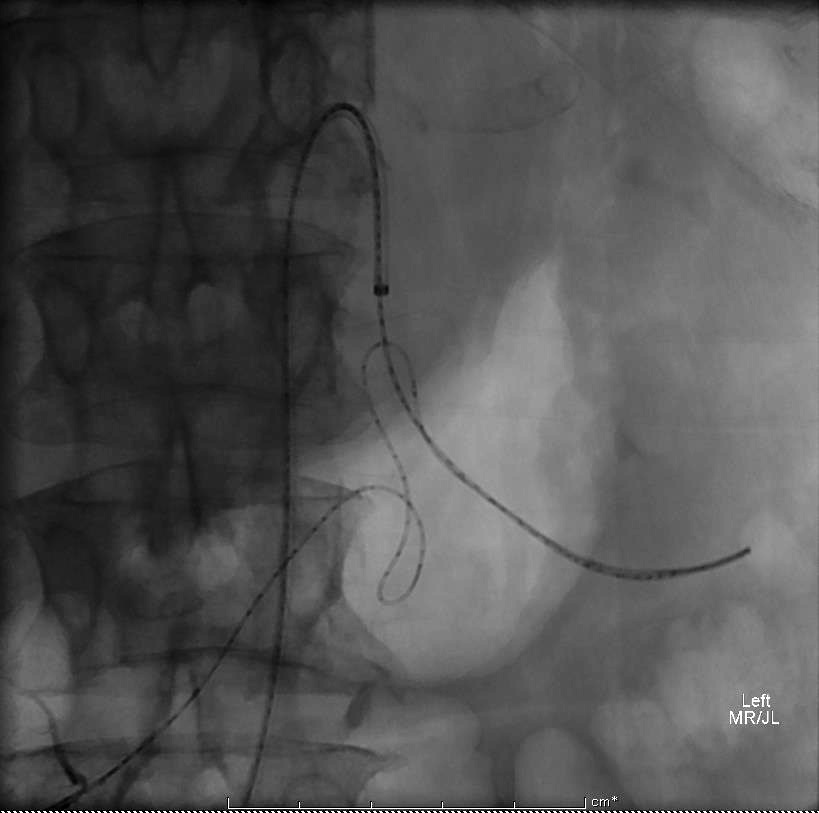

| 非食道静脉曲张消化道出血的血管内治疗围手术期相关并发症发生率大约在10%左右,包括血管造影相关并发症、血管收缩剂使用相关并发症和栓塞相关并发症和死亡。临床相关的患者基本条件如年龄和伴发疾病与围手术期相关并发症强烈相关;而操作相关围手术期并发症包括与临床结果无关的并发症和急性肠缺血并发症(<5%)。 1. 血管造影相关并发症 (1)穿刺部位相关并发症 ( Puncture site complications ) (2)CIN -造影剂肾病(Contrast-induced nephropathy:此病人人群较高 (3)其它全身并发症:心肌缺血、败血症和过敏反应 2. 血管收缩剂使用相关并发症:心律失常、血栓,心肌缺血,体液潴留(fluid retension) 3. 栓塞相关并发症[6,8] (1)肠道缺血(Bowel ischemia )/梗死:发生率0-4%;下消化道出血>上消化道出血;微粒>明胶海绵颗粒>弹簧栓子;缺血性改变大多数是自限性的。肠梗塞[5] :9%。 (2)意外栓塞:(?%)但罕见 女,74岁 多种疾病和间歇性消化道出血,红细胞标记扫描出血部位被定位在右下腹,回场末段或升结肠。早先血管造影和内视镜为阴性。两天后再次大出血。

(3)弹簧栓子释放位置不良或移位(1-3%)。

预防推式弹簧栓子释放时位置不良可选择正确直径大小或使用可脱微弹簧栓子。 (4)痉挛/夹层(2%)